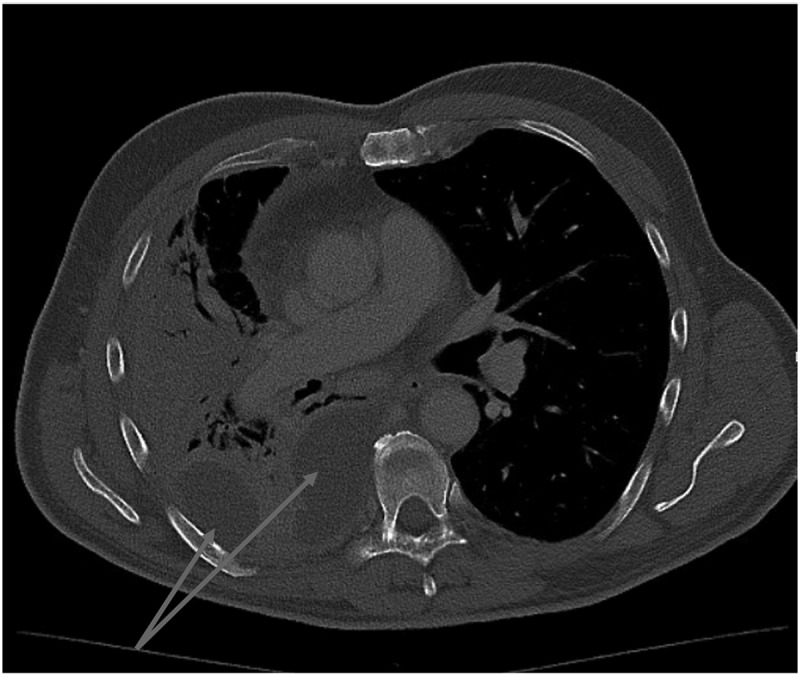

Serotype 3 pneumococcal infection can cause severe invasive disease, even in immunocompetent adults, and is potentially preventable by vaccination. Invasive pneumococcal disease caused by serotype 3 is currently the most frequent serotype found in adults in Denmark. In this report, we present a 62-year-old immunocompetent man diagnosed with a severe pleural empyema caused by serotype 3, requiring a long course of antibiotics. The patient experienced clinical improvement, and follow-up imaging showed near-complete resolution of lung infiltrates. We also review the epidemiology of serotype 3 invasive pneumococcal disease in adults in Denmark and discuss the challenges related to serotype 3 and effective vaccines.